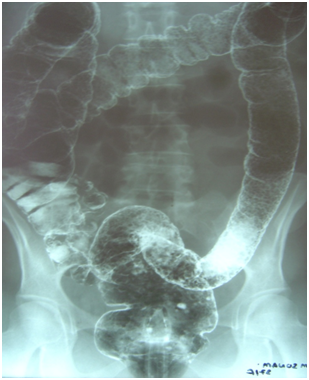

A female of 37years presented with per rectal bleeding for 8years to the Department of Radiology of Tribhuvan University Teaching Hospital in 2007 for a barium enema study. Her elder brother had similar symptoms and he had undergone colectomy. Her late father also suffered from recurrent episodes of per rectal bleeding. Two big brothers died in childhood. Her sister had also died of distension of abdomen. She has two children who are asymptomatic. Her double contrast barium enema study shows multiple round filling defects involving the whole colon including the rectum (Figure 1). Barium study of her brother showed irregular large filling defect in the rectum due to malignant mass in addition to multiple small filling defects (Figure 2).

Figure 1 Double contrast barium enema study of the patient.